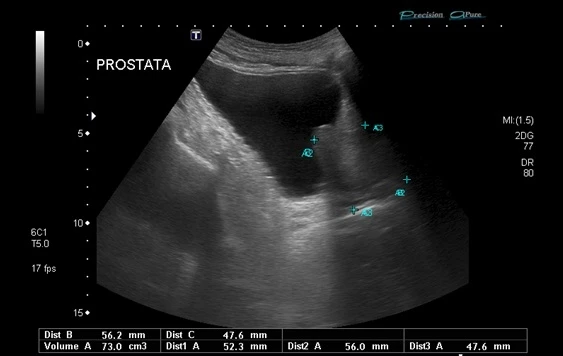

biopsia de próstata

A biópsia de próstata é um procedimento realizado para diagnosticar o câncer de próstata. Durante o procedimento, o médico insere uma agulha na próstata para retirar pequenas amostras de tecido. Essas amostras são examinadas em laboratório para determinar se há células cancerígenas presentes. A biópsia é geralmente realizada após um exame de sangue de PSA elevado ou um exame retal anormal. Embora a biópsia possa ser desconfortável, é um procedimento seguro e eficaz para diagnosticar o câncer de próstata. Se você tiver dúvidas sobre a biópsia de próstata, consulte um urologista. A DK Urologistas oferece serviços de diagnóstico e tratamento de câncer de próstata.